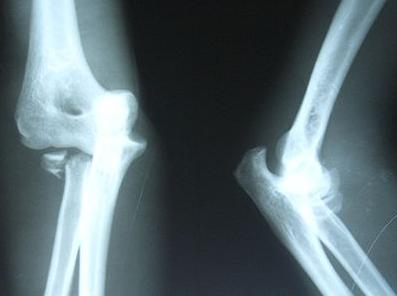

骨不连是属于骨折后的并发症,骨折端位不好,受到药物的刺激,过度的牵引,严重开放性骨折,软组织损伤较大,血管受损伤挤压造成患部血运不良,骨组织感染,内固定材料过敏等,只要达到一定的时间强度的刺激,都会产生一系列的神经、内分泌、免疫功能的改变而引发骨不连。

骨不连只是骨髓炎发生时的一种情况,但是不是同一种疾病,骨不连在治疗不及时会转变成骨髓炎,这时需要引起人们的重视的。再骨折手术治疗的过程中,如果出现延迟愈合或是骨不连时,就要好好研究一下真正的病因所在。